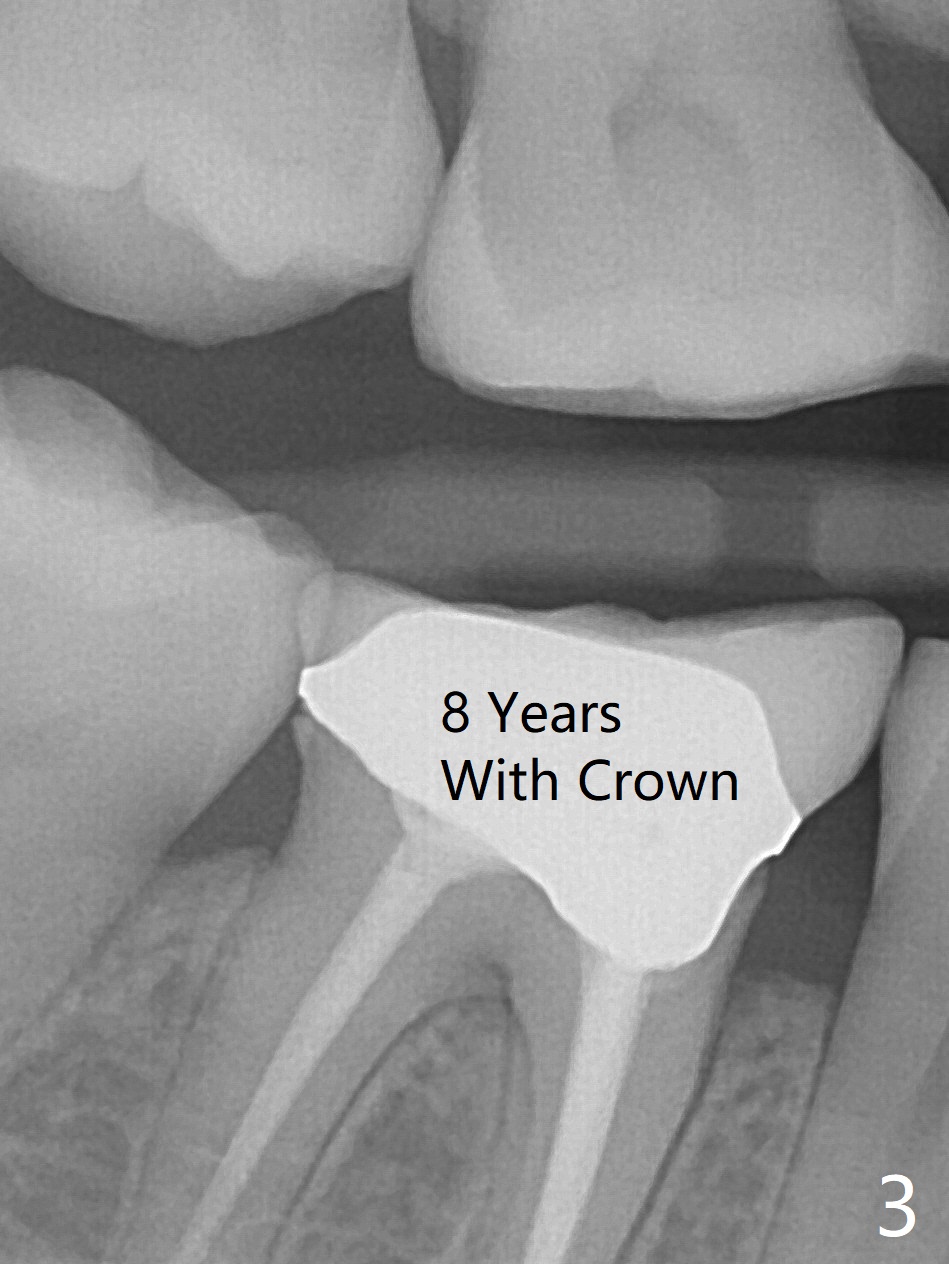

A 47-year-old woman with one carious tooth in her mouth (at #30) received RCT 14 years ago (Fig.1). The molar survives without crown for 3.5 years (Fig.2) and with crown for 8 years (Fig.3). The tooth has 2nd decays 10 years post crown (14 years post RCT, Fig.4 *). The crown dislodges 2 months later (Fig.5). Does the crown inadvertently reduce the longevity of the tooth simply hampering oral hygiene? After osteotomy until 4.5x10 or 13 mm IS drill with guide and 5 mm Bicon reamer free hand, place either 5x6 or 11 mm Bicon implant (Fig.6). Keep the black insertion plug to hold periodontal dressing or a provisional, which will be bonded to the neighboring tooth. Prepare PRFx1 for sticky bone around the not-so-stable implant. A 5x11.5 mm bone-level implant is planned by CT (Fig.7). Socket shield will be conducted to reduce buccal plate collapse. If the osteotomy depth is 10 mm due to limited mouth opening, place 4.5x6 mm Bicon implant. Otherwise 4.5x8 mm one. Return to Lower Molar Immediate Implant, Prevent Molar Periimplantitis (Protocols, Table), Trajectory II, Metronidazole Early Intervention Xin Wei, DDS, PhD, MS 1st edition 09/01/2019, last revision 11/10/2019